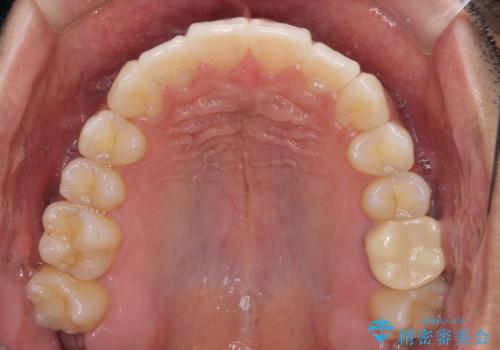

前歯のデコボコを治したい インビザライン矯正治療

- 前歯のデコボコを治したいとのことで来院された患者様です。

上下顎ともに歯列全体の後方移動とIPR(歯と歯の間を削る)によってデコボコが解消するように設計し、インビザラインにより治療を行うこととしました。

毎日22時間以上しっかりとマウスピースを装着していただいたので、スムーズに治療が進みました。歯と歯の間を削ることでうまくスペースコントロールでき、1年強で終えることができました。